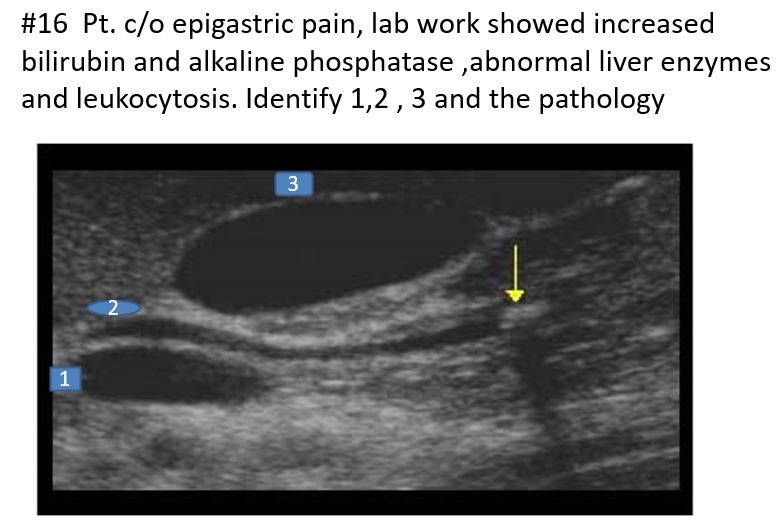

1. Portal Vein

2. Common Bile Duct

3. Gallbladder

Pathology: Choledocholithiasis

Symptoms

Increased direct bilirubin

Leukocytosis

Increased alkaline phosphatase

Abnormal liver enzymes

Choledocholithiasis